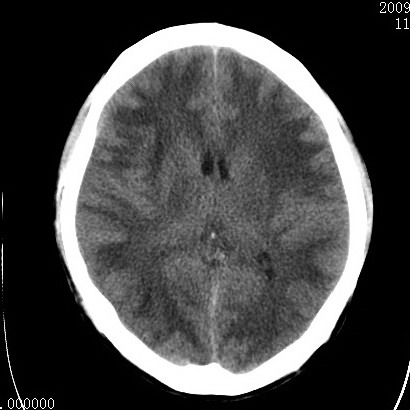

以下是引用余辉在2009-4-9 17:34:00的发言:[br]双侧脑白质对称性弥漫性密度减低,脑室脑沟裂池变小,双侧豆状核对称低密度,脑干对称性低密度,考虑1中毒性脑病2电解质异常(低钾钠等)3代谢异常及维缺乏等,进一步检查。